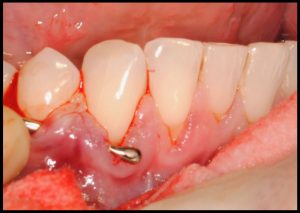

Objetivos periodontales: Mediante ingerto de tejido conectivo subepitelial de paladar con técnica de tunelización.

- Cobertura radicular en recesiones múltiples

- Estabilidad periodontal mejorando el biotipo gingival

- Mejora sensibilidad

Fotografías del proceso: